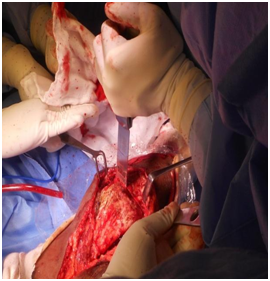

Because knee surgery requires deep flexion at hip, we decided to replace hips first. Patient was given general anesthesia, put in lateral position, and operated using posterior approach. Because head was not dislocatable, in situ neck osteotomy had to be done and then acetabulum was reamed through the ankylosed head taking care of the acetabular walls and positioning. Extensive soft tissue releases were required to correct the deformities and a primary non-constrained uncemented implant was used (Stryker). Figure 5 owing to the osteoporotic bone, there was undisplaced spiral fracture of right proximal femur which was taken care of using cerclage wires. Adductor tenotomy was done postoperatively as the tendons standout only after taking down the ankylosis.

Figure 5 Postoperative radiograph showing bilateral total hip.